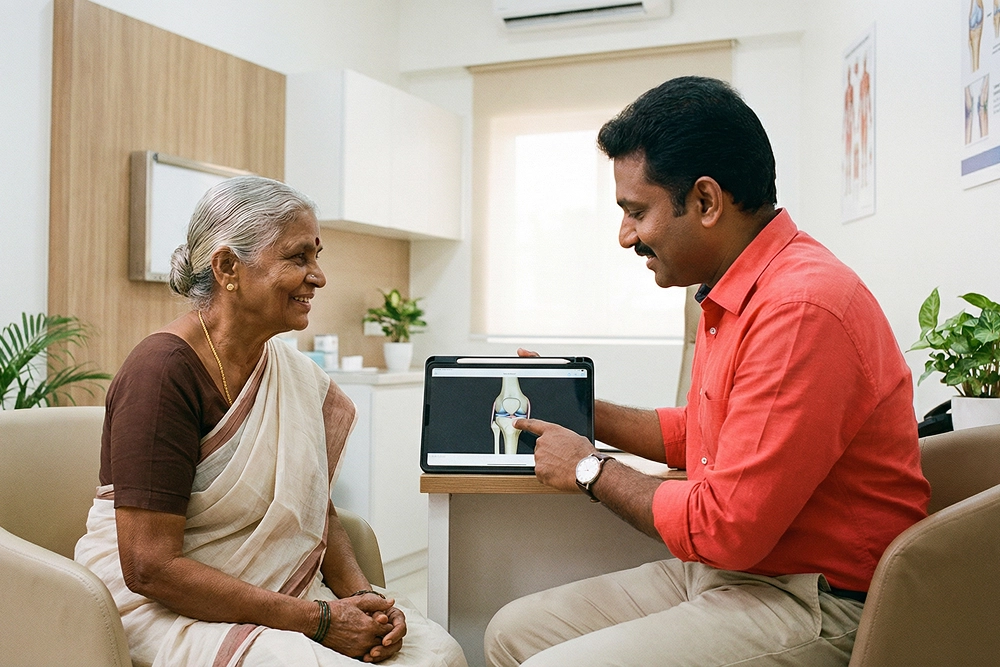

The Orthopaedics department at Anandam Hospitals is a state-of-the-art centre dedicated to the end-to-end care of all musculoskeletal conditions across every age group, with a special focus on children, whose bone and joint requirements differ significantly from those of adults. Led by a distinguished team of world-renowned clinical experts, this multidisciplinary institute delivers comprehensive, personalised treatments designed to enhance our patients' overall quality of life. We specialise in joint replacements, the treatment of sports injuries, trauma management, congenital defects, and spinal problems.

Our experts are supported by robust nursing and paramedical teams, seamlessly utilising advanced diagnostic and surgical technologies to provide top-notch clinical care. Our primary aim is to ensure that each patient receives comprehensive, gentle care, enabling them to confidently return to their lives. From advanced pain management to specialised occupational therapy, we are committed to providing personalised treatment plans and therapies that reside at the very forefront of orthopaedic care, employing the latest medical technology, techniques, and protocols.

We feature a dedicated, multidisciplinary team of joint-specific doctors and expert therapists.

Dedicated experts for each joint of the body are backed by specially trained nurses and occupational therapists who work together to ensure complete patient well-being, both pre- and post-surgery, guaranteeing optimal outcomes.

At Anandam Hospitals, experts from across various disciplines and specialties unite to comprehensively assess patients, offering the best possible treatment plan utilising the most advanced medical technology, techniques, and clinical protocols.

Our super-specialist doctors consistently provide the highest quality of care through a deeply integrated, team-based, doctor-led clinical model. Having trained at some of the world’s most renowned medical institutions, our highly experienced doctors stand as distinguished experts within their respective specialties.

Our physicians work full-time and exclusively across the Anandam Hospitals network. In addition to offering super-specialised care within their own fields, the organisational structure of Anandam Hospitals enables every doctor to actively help create a culture of seamless collaboration and multispecialty care integration.